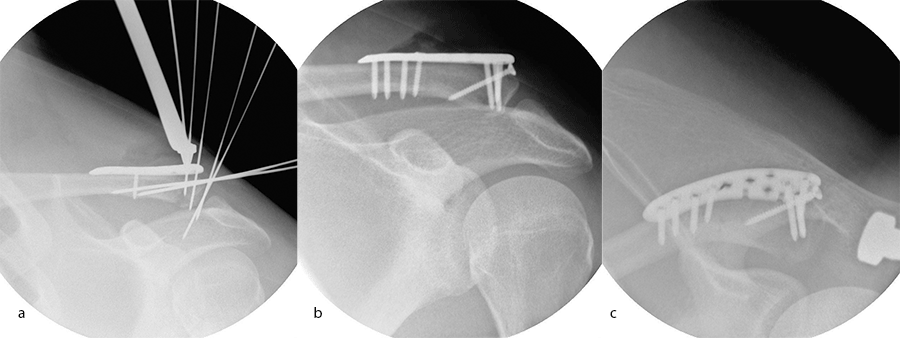

Case 1: lateral plate

A 30-year-old man sustained a lateral fracture to his left clavicle following a fall from his bike (Fig 9). Intraoperative images indicate plate placement and screw insertion (Fig 10). Intraoperative image revealing usage of sutures through the plate for soft- tissue fixation (Fig 11). Image shows the fracture healing at 8 weeks' follow-up (Fig 12).